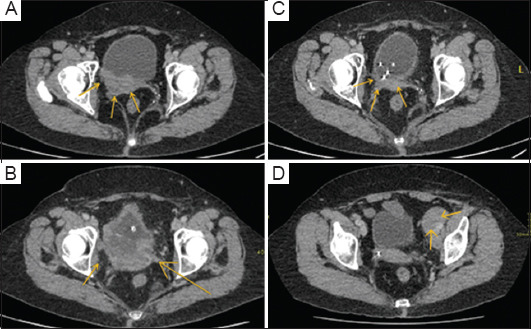

Case presentation: Presented here is a 61-year-old female with high-grade urothelial carcinoma who had initially undergone chemotherapy, followed by treatment with atezolizumab (an anti-programmed death-ligand 1 antibody). Due to disease progression and symptoms, she received palliative RT alongside continued immunotherapy. Post-RT staging scans showed a significant reduction in the size of the bladder mass and a marked improvement in the patient's quality of life. Although this case did not demonstrate a definite abscopal effect, it underscores the potential benefits of combining immunotherapy and RT.